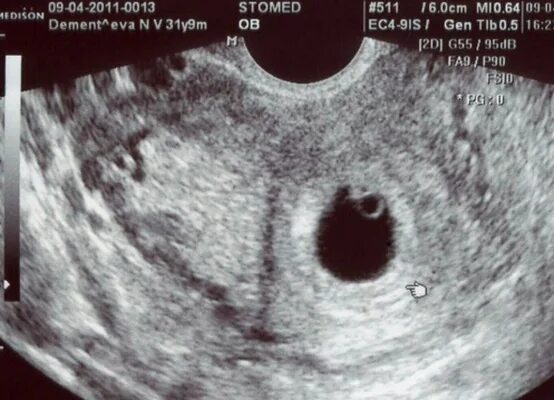

Сколько прикрепляется плодное